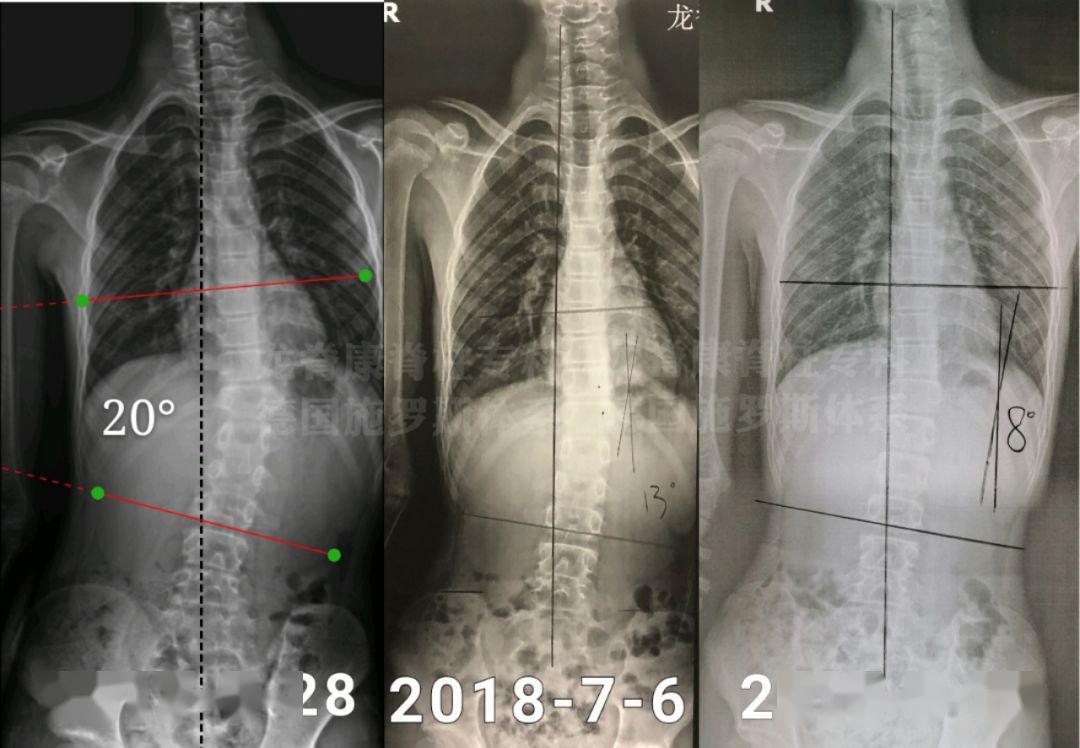

另外,先天性脊柱畸形可发生于以下方面:出生后下肢畸形或尿道异常;背部皮肤,特别是脊柱部位,出现色素沉着、异常毛发或肿块;上半身较短的儿童与其身体长度不成比例。对于可疑体征的患者,应进行 X线检查,发现有脊柱畸形或肋骨畸形,测量并记录畸形程度。

先天脊柱侧凸的x线表现具有以下“s”型特征:短曲线和锐曲线。

将患儿从腋下悬吊,观察脊柱侧弯的僵硬硬度和柔韧性,检查神经系统,观察肌张力是否增高或减低,是否有其它先天畸形。拍摄全脊柱悬吊位和仰卧位正侧位片,观察肋椎椎体角度的差异。体格检查可以诊断出明显的脊柱侧弯,但脊柱侧弯的角度仍需 x线测量。